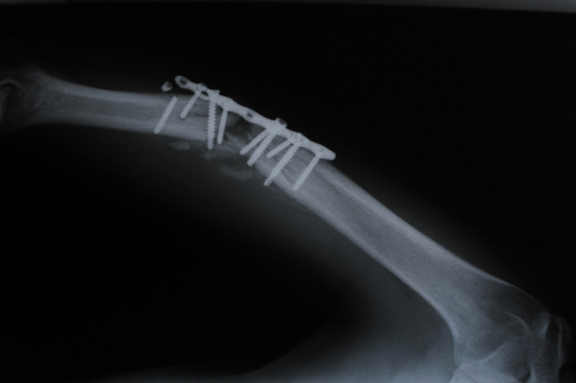

A 28-year-old male diagnosed with closed humerus shaft fracture due traffic accident without neurovascular injury. He was treated with open reduction and plate fixation at another hospital four months ago. (Figure 1A-B) Postoperative period was uneventful. However, there was a lack of union after 12 weeks. (Figure 2) He was presented to our outpatient clinic with severe pain after a minor trauma. The plain radiographs revealed a non-union of humerus shaft fracture with loss of reduction and implant failure with a broken screw. (Figure 3) There was no evidence of infection on clinical examination and C-reactive protein level was also normal. The patient was diagnosed with atrophic non-union with implant failure and offered revision surgery with implant removal, bone grafting and fixation with a longer and thicker plate. However, the patient did not accept revision surgery demanded conservative treatment. Closed manipulation (Figure 4A-B) under sedation and a Sarmiento type brace cast was applied. Although the reduction was good, the patient was informed of high risk of ineffectiveness of this treatment method. During monthly follow-up, there was no loss of reduction again, and at the fourth month follow-up after closed manipulation solid bony union was achieved without any deformity. (Figure 5A-B)

Figure 1: (A, B) Inappropriate plate fixation of humeral diaphysis fracture.

Figure 4: (A, B) Implant after close reduction.